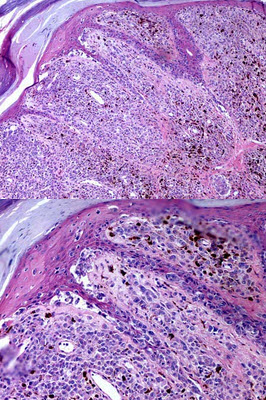

患者,36岁,男,右足底黑痣迅速增大,表面溃烂1个月。手术切除送检。

第1题,共2个问题

(单选题)镜下如图所示,真皮浅层肿瘤细胞呈巢状或片状排列,部分区侵入表皮生长,细胞核大,核仁明显,易见核分裂像。最可能的诊断是( )

A:皮肤慢性溃疡

B:皮内痣

C:皮肤交界痣

D:恶性黑色素瘤

E:以上均不是

第2题,共2个问题

(单选题)关于该病变说法不正确的是( )

A:来源于上皮组织

B:以足底部和外阴、肛门周围皮肤好发

C:来源于神经外胚叶组织

D:可由交界痣恶变而来

E:大多预后很差